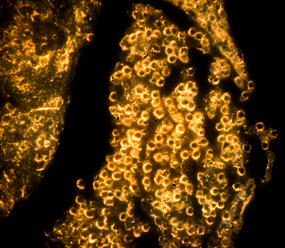

«Несмотря на длинный и немного пугающий названиями список компонентов, все они в высокой степени биосовместимы и активно используются в биомедицине, — пояснил один из соавторов работы, научный сотрудник лаборатории „Биомедицинские наноматериалы“ НИТУ „МИСиС“, PhD Роман Акасов. — Полученная смесь перемешивается под действием ультразвука, формируя двойную эмульсию вода-масло-вода. Дальше ее можно облучить ультрафиолетом, в результате чего в растворе происходит формирование наночастиц золота. При этом частицы окружены полимером, который придает им свойства биосовместимости и устойчивости в водных растворах. Эмульсия при этом превращается из беловато-прозрачной в красную, что является индикатором успешного проведения фотополимеризации. Размер частиц в наших экспериментах составлял около 100 нанометров, что привлекательно для биомедицинских применений, и частицы не были токсичны для клеток».

Также в работе авторам удалось показать, что золотые наночастицы накапливаются в цитоплазме клеток — как опухолевых глиомных, так и иммунных клетках макрофагах. Это открывает возможности индивидуальной диагностики и терапии опухолевых заболеваний. В дальнейшем планируется модифицировать поверхность наночастиц специальными молекулами, чтобы адресно находить опухоль в организме. Однако исследователи предлагают и другой вариант использования своего метода — как биоконструктор.